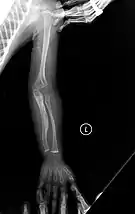

The main symptom of osteogenesis imperfecta is fragile, low mineral density bones; all types of OI have some bone involvement.[5] In moderate and especially severe OI, the long bones may be bowed, sometimes extremely so.[28] The weakness of the bones causes them to fracture easily; a study in Pakistan found an average of 5.8 fractures per year in untreated children.[29] Fractures typically occur much less after puberty, but begin to increase again in women after menopause and in men between the ages of 60 and 80.[1]: 486

- Type V – Having the same clinical features as type IV, it can be clinically distinguished by observing a "mesh-like" appearance to a bone biopsy under a microscope. Type V can be further distinguished from other types of OI by the "V triad": an opaque band (visible on X-ray) adjacent to the growth plates; hypertrophic calluses (abnormally large masses of bony repair tissue) which form at fracture sites during the healing process; and calcification of the interosseous membrane of the forearm,[50] which may make it difficult to turn the wrist.[1]: 429 Other features of this condition may include pulled elbow, and, as in other types of OI, long bone bowing and hearing loss.[64] Cases of this type are caused by mutations in the IFITM5 gene on chromosome 11p15.5.[64][49] The separation of type V from type IV OI, its clinical type, was initially suggested even before its genetic cause was known, by Glorieux et al. in 2000.[50][65] Type V is relatively common compared to other genetically defined types of OI—4% of OI patients at the genetics department of the Brazilian Hospital de Clínicas de Porto Alegre were found to have it.[66]